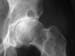

Anteroposterior (AP) radiograph of the hip reveals severe superior migration of the femoral head (which reflects loss of articular cartilage), subchondral sclerosis, prominent osteophytes, and a large Egger cyst in the superior acetabulum. Mild flattening of the superior aspect of the femoral head is present.

The traumatized subchondral bone may also undergo cystic degeneration, which is attributable either to osseous necrosis secondary to chronic impaction or to the intrusion of synovial fluid. Osteoarthritic cysts are also referred to as subchondral cysts, pseudocysts, or geodes (the preferred European term) and may range from 2 to 20 mm in diameter. Osteoarthritic cysts in the acetabulum (see the image below) are termed Egger cysts.